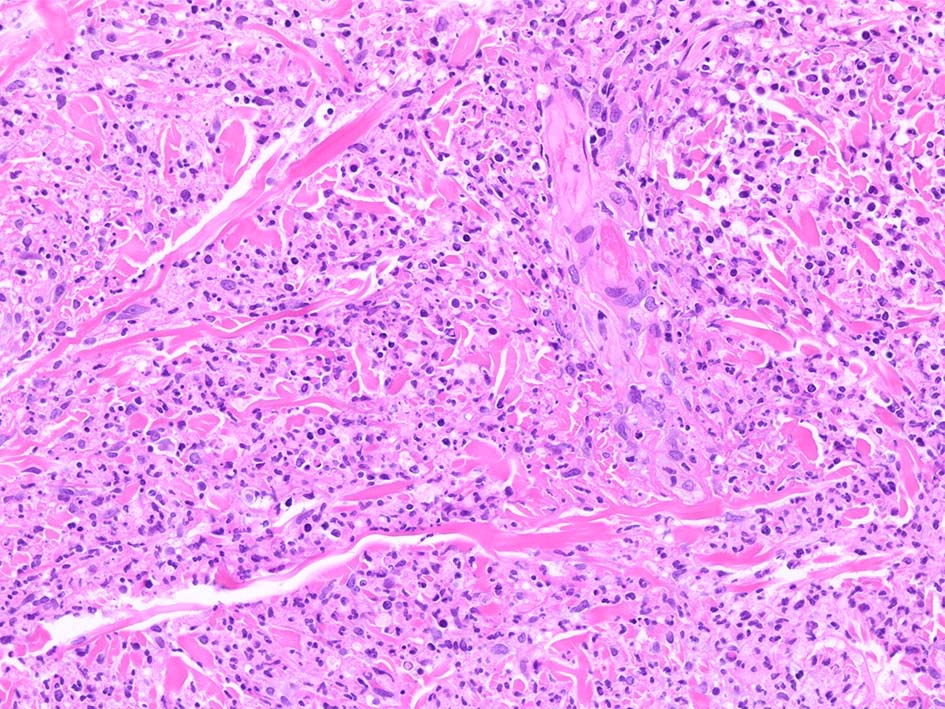

典型疹は真皮の好中球浸潤より始まる. 病初期では, 好中球浸潤は表皮に及ばない. 病期が進むにつれ, 2次的好中球浸潤が認められるようになる.

真皮上中層で広範囲に好中球が密に浸潤する所見がSweet病の最大の特徴. 好中球活性が亢進し, apoptosisを起こして核塵(核破砕物)がみられることが多い. 浸潤が顕著になると真皮上中層が浮腫をきたして, 皮疹が隆起する.

HE x40. 表皮下水疱あり. 真皮上層は浮腫状. 真皮から皮下組織にかけて, 多数の好中球が浸潤している. リンパ球, 好酸球が混在, 核破砕物を貪食するマクロファージが増加. 膠原線維にはところどころ変性が見られる.

真皮上層には核破砕物が多く, 好中球浸潤が認められる. 慢性炎症性細胞も浸潤している.

フィブリノイド壊死を呈する血管炎は認められない.